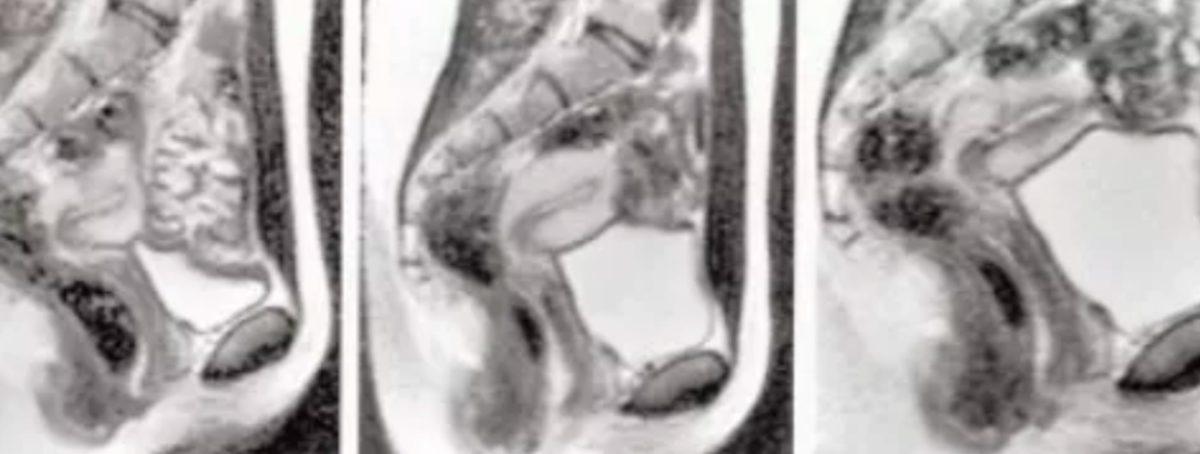

Araştırmacıların bulgularına göre, misyoner pozisyonundaki seks esnasında penis, bumerang şeklini alıyor, uzunluğunun üçte biri penisin kökünden oluşuyor. Kadınların uyarılması sırasında ise rahim genişliyor ve rahim duvarları uzuyor.

Önce, sırt üstü yatan kadınların leğen kemikleri tarandı. Sonrasında erkeklere odaya girmeleri ve kadınlarla misyoner pozisyonunda cinsel ilişkiye girmeleri istendi. Daha sonra erkeklerin odayı terk etmesi ve kadınlardan kendi kendilerine orgazm olmaları talep edildi. Kadınlar, görüntü alınabilmesi için orgazm olmadan önce araştırmacıları bilgilendirdi ve kadınlar orgazm olduktan 20 dakika sonra son fotoğraf elde edildi.

Amaç, manyetik rezonans görüntüleme (MRI) tarayıcısında cinsel birleşme sırasında insanların cinsel organlarının görüntüsünü almak ve o dönem seks hakkındaki fikirlerin doğru olup olmadığını test etmekti. Araştırmaya, 1'i sokak akrobatlarından oluşan 8 çift, 3 de bekar kadın katıldı. 13 deneyin yapıldığı araştırma boyunca 3 çift ikişer kez ilişkiye girerken bekar kadınlar partnerleri olmaksızın orgazm oldu.